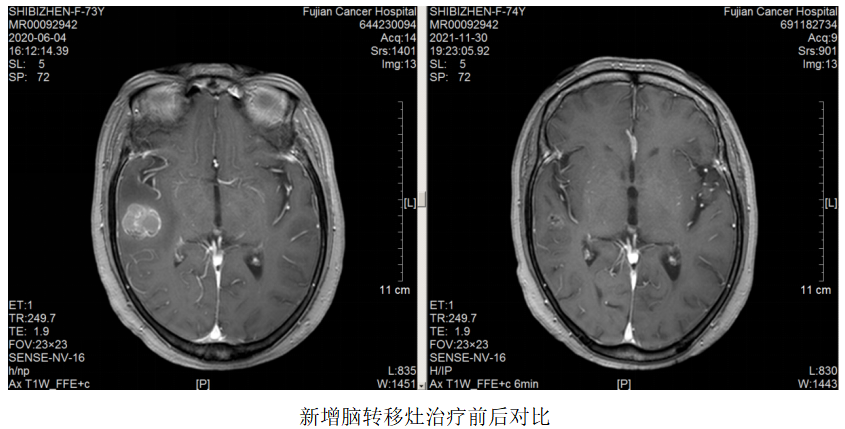

再次放疗:2020.06.04复查颅脑MR:原左侧额、枕叶脑转移瘤较前缩小,右侧颞叶新增转移瘤,于2020.6.15-6.26予脑转移灶调强放疗DT3000CGy/10F。

继续维持治疗:新增右侧颞叶脑转移灶,配合脑转移局部放疗,其余病灶好转,继续原方案全身治疗。

2021.5.18开始患者因经济原因改予汉曲优治疗至今,肿瘤进一步退缩,疗效评估PR。